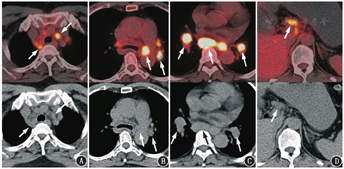

本例患者在开始抗PD-L1治疗后迅速出现了淋巴结病变明显增多、增大;继续维持治疗,淋巴结的病变又趋于稳定,变化不明显。如果考虑抗PD-L1治疗后新出现的淋巴结病变都是转移,是肿瘤的超进展,那么后续治疗过程中的变化并不符合肿瘤超进展的表现。仔细观察开始抗PD-L1治疗后出现的淋巴结病变,大多分布在肺门、气管周围,双侧分布较对称,淋巴结密度较均匀,没有明显的坏死、融合,这种PET/CT上的表现很符合结节病的代谢、形态、分布特征(图2)。

ICIs治疗除了可能出现假进展,还会引起自身炎性毒性反应,称为免疫相关不良反应(immune-relatedadverseevents, irAEs),结节病样反应就是irAEs的一种。结节病样反应在抗PD1或PD-L1治疗中发生概率并不高,通常无症状,由影像检查发现。研究推测ICIs的结节病样反应的机制与系统性结节病相似,以辅助性T细胞(helper T cell, Th)1反应为主。ICIs引发细胞介导的免疫反应及随后免疫原性肿瘤细胞破坏可能暴露出促肉芽肿炎性反应形成新抗原,从而导致结节病样反应。与系统性结节病相似,irAEs中的结节病样反应最常累及淋巴结、肺及皮肤,偶尔也会有中枢神经系统、垂体、脾、骨受累[7]。典型结节病样反应的18F-FDG PET/CT表现与系统性结节病一致,为对称性的双肺门及纵隔淋巴结肿大,密度均匀,不伴坏死,可伴双肺多发淋巴管周围分布的间质结节、斑片或团块、磨玻璃影等,形态多样,代谢增高,可伴腹腔淋巴结受累[8]。本例患者根据新出现淋巴结的形态、分布、代谢特点、以及ICIs治疗过程中的变化,要考虑出现结节病样反应的可能。